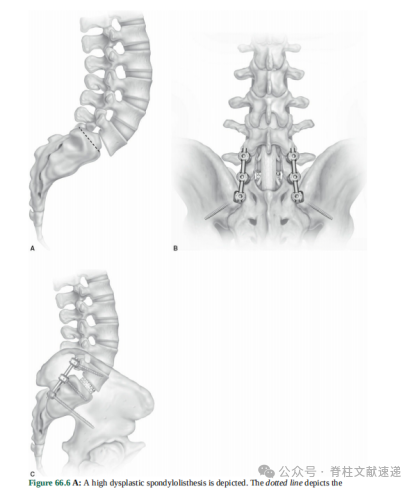

复位内固定技术是由著名的Harms教授提出,Shuffebarger教授等逐渐发展起来。笔者认为该技术的核心理念有:远端两钉固定、临时撑开、L5神经根松解、必要时骶骨穹窿切除、椎间支撑后方加压。下面简述操作步骤。

2.螺钉和临时撑开

腰3、4椎弓根螺钉和S1、S2AI螺钉首先置入,腰3、4椎弓根螺钉沿横突根部置入可保护关节囊、连接棒更靠外,不影响后续操作。S1螺钉进钉点选择要偏下一些,朝向骶骨岬皮质固定。L3、4和S2之间安装连接棒临时撑开作用。切除腰5椎板,经常需要同时切除部分腰4椎板。S2螺钉主要为了保护S1螺钉,确保固定牢靠。

5.复位、支撑、加压

安装L5螺钉,在S1、S2螺钉安装连接棒,并下压至L4、L5钉尾内,双侧交替拧入提拉。过程要非常缓慢,多次神经电刺激评估L5神经根、观察螺钉是否松动。

IV度滑脱复位至20%-40%滑脱即可,得到良好的植骨融合空间和腰椎曲度,最好不要完全复位,完全复位时神经根损伤导致足下垂几率明显增加。

进一步将L5/S1间隙进行处理,得到良好植骨床,放置松质骨粒和8mm Cage支撑。通过连接棒后方加压,增大前凸、减少神经根张力。